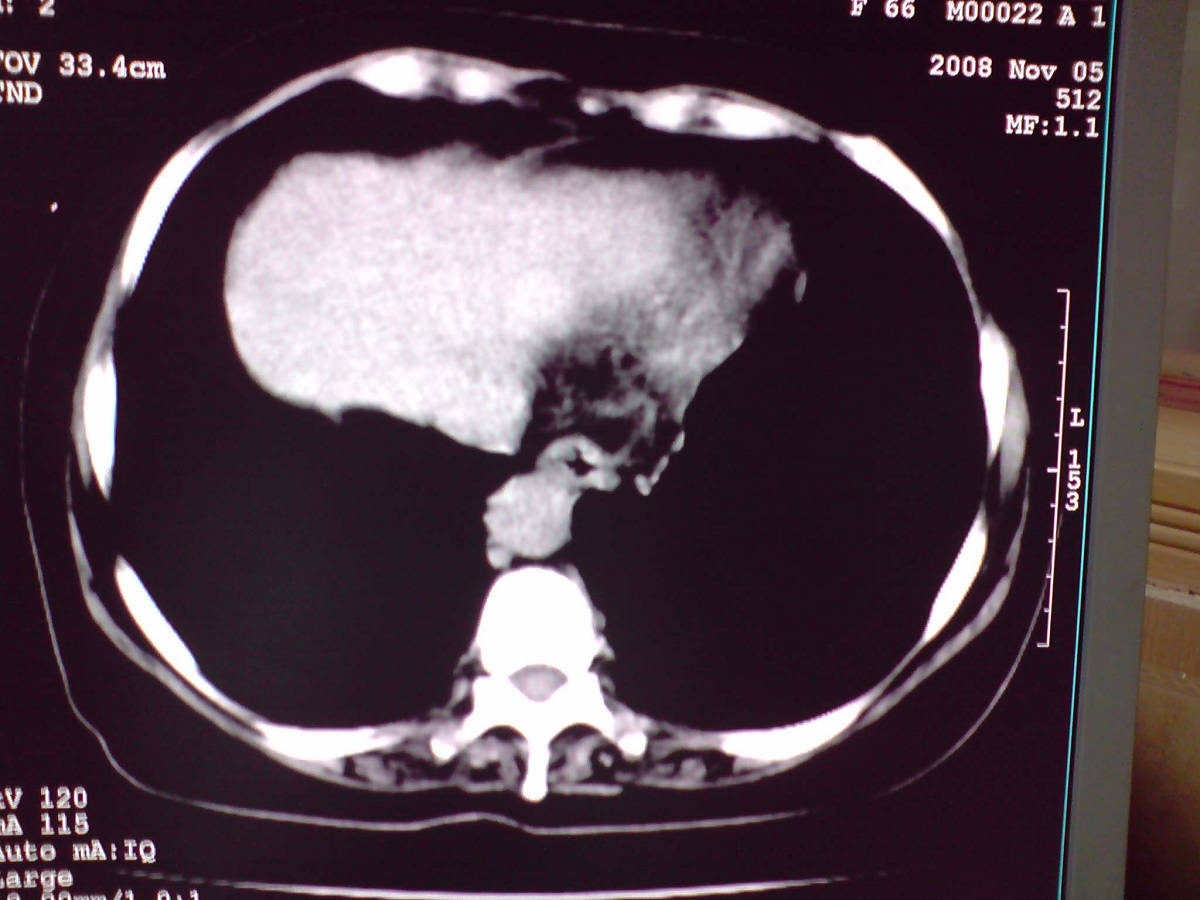

小网膜区见类圆形软组织密度肿块,密度不均,内见不规则低密度区,与肝左叶分界模糊,肝脏体积缩小,密度不均匀,边缘呈波浪状,尾状叶明显增大,脾脏下缘明显超出肝脏下缘。

意见:肝硬化并外生性肝癌,建议增强扫描。

肝脏比例失调,形态失常,外缘呈波浪状,腹腔内肿块内见低密度区并与肝脏界限欠清

考虑外生性肝癌,左肺下叶占位,肝硬化

有肝硬化背景,肝胃间隙见不规则形,且密度不均匀的占位性病变,与肝左叶分界不清,首先考虑外生性肝癌可能性大,不排外肝胃间隙恶性占位肝脏受侵可能性。左肺下叶结节影,其内见空泡征,边缘见毛刺,从一元化的角度首先考虑转移。

1 肝脏各叶比例失调,形态失常,外缘呈波浪状。右叶萎缩,左叶 尾叶增大。2 腹腔内软组织密度肿块,低于肝实质密度,内见低密度区,并与肝脏界限欠清。腹膜后见肿大淋巴结,并与腹腔肿块关系密切。3 左肺下叶肿块,见边缘毛刺征及胸膜凹陷征,并与近肺门侧见异常血管相连。

综合考虑:左下肺周围性肺癌伴腹腔 腹膜后淋巴结转移!另:肝硬化!

1肝胃韧带区域一肿块,肿块上缘与肝左叶相连。肝硬化。考虑肝外生型肝癌可能性大,不除外间质瘤。2左肺下叶背段一结节,有偏心性空洞,长毛刺,其周有多发小结节。考虑结核可能性大。

一元论:肝硬化、外生性肝癌并左肺转移;但不除外左肺周围型肺癌可能。

感谢大家的讨论,今天拿到病理结果是肝细胞癌